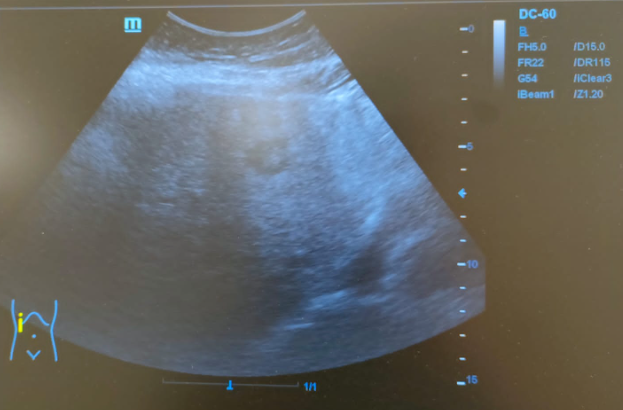

Hallazgos ecográficos

Hígado de tamaño normal, contornos ligeramente nodulares, alteración de la ecoestructura compatible con hepatopatía crónica. Nódulo hipoecoico de contornos irregulares en lóbulo hepático izquierdo de 16x24mm sin captación Doppler.